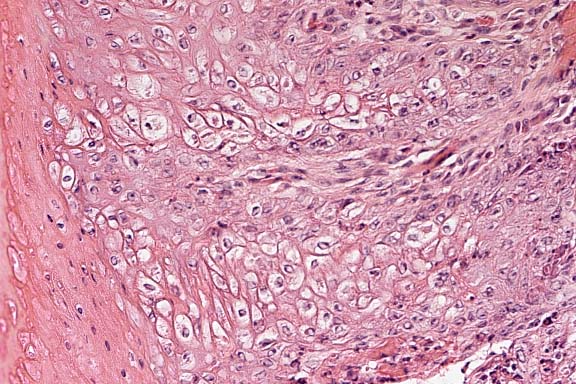

Case 15-1. Liver. There is increased dense fibrous tissue in the portal area between 2 hepatic lobules. Remaining hepatocytes are filled with cytoplasmic hemosiderin. 20X

1. Liver: Brown granular pigment accumulation, hepatocytes and Kupffer cells, diffuse, severe, with diffuse fibrosis, biliary hyperplasia, hepatocellular loss, and multifocal nodular hyperplasia, Salers cross, bovine.

Conference Note: The brown granular pigment stained blue with Perls iron stain, confirming that it is hemosiderin.